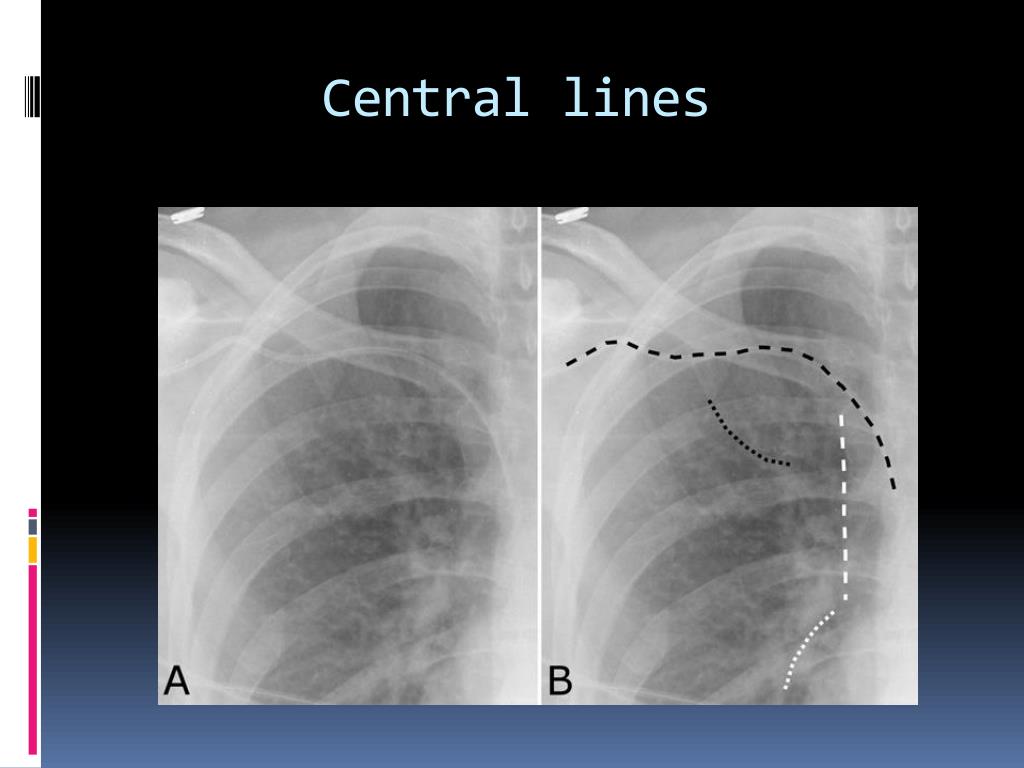

36. Some life lines can be assessed • Central line • Tracheostomy • Nasogastric tube • ET tube

38. Central lines